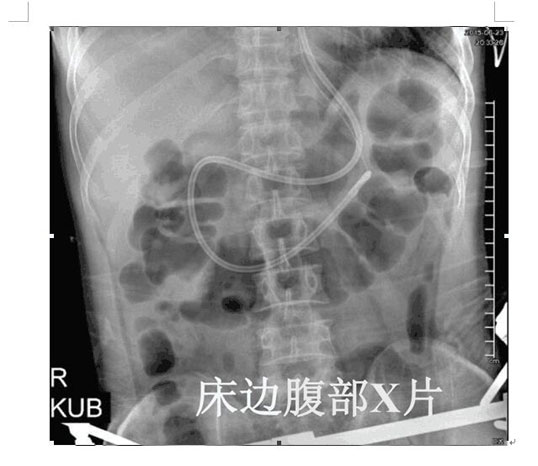

2017年4月22日,ICU成功開展了第一例床旁盲插經(jīng)鼻空腸管置入術(shù)并獲得成功。截止目前已為三位患者完成該術(shù),均為一次性盲插置管成功,臨床反映良好。此項技術(shù)的成功應(yīng)用,填補了我院在該護理技術(shù)領(lǐng)域的一項空白,標志著ICU的護理技術(shù)水平邁上了一個新的臺階。

以往選擇在X線下或者使用胃鏡協(xié)助置入鼻空腸管,患者痛苦大且受輻射影響。而床旁徒手盲插經(jīng)鼻空腸管植入術(shù)是臨床護士在不依賴于其他輔助設(shè)備的情況下,通過一定的置管技巧,將管道插至十二指腸或空腸。此法省時、費用低、操作方便、損傷小,尤其對胃蠕動功能差的患者,不易引起食物反流、誤吸。鼻空腸管不僅可以從管內(nèi)注入營養(yǎng)液,而且還可以進行胃腸減壓,值得臨床推廣。